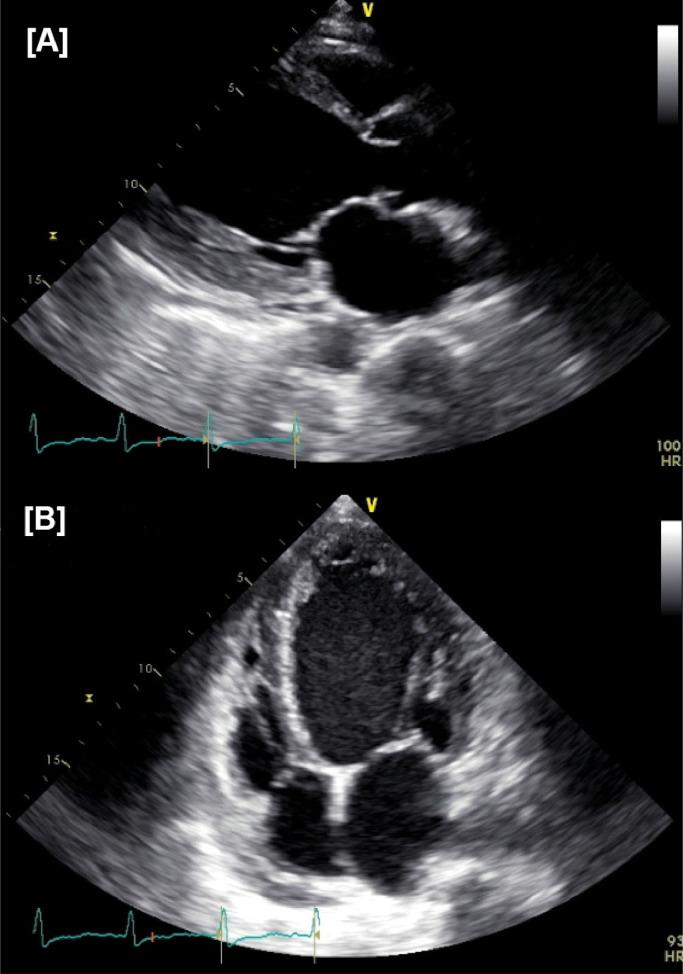

Heart failure (HF) is a clinical syndrome with a wide spectrum of presentations and an even wider array of etiologies. Anthracyclines such as Doxorubicin, Daunorubicin, Idarubicin, and Epirubicin have demonstrated increased risk of HF with significant morbidity and mortality. We present an interesting case report of a patient with a history of breast cancer treated with Doxorubicin who presented with symptoms of HF who had a comprehensive evaluation that excluded the most common etiologies, narrowing our diagnosis to late onset doxorubicin induced HF with on-going recovery after initiation of guideline-directed medical therapy.

心力衰竭(HF)是一种临床表现多样、病因更为广泛的临床综合征。阿霉素、柔红霉素、伊达比星和表柔比星等蒽环类药物已显示出发生HF的风险增加,且具有显著的发病率和死亡率。我们报告了一例有趣的病例,该患者有乳腺癌病史,曾接受阿霉素治疗,出现了HF症状,经过全面评估排除了最常见的病因,将诊断范围缩小为迟发性阿霉素诱导的HF,在开始指南指导的药物治疗后病情正在恢复。